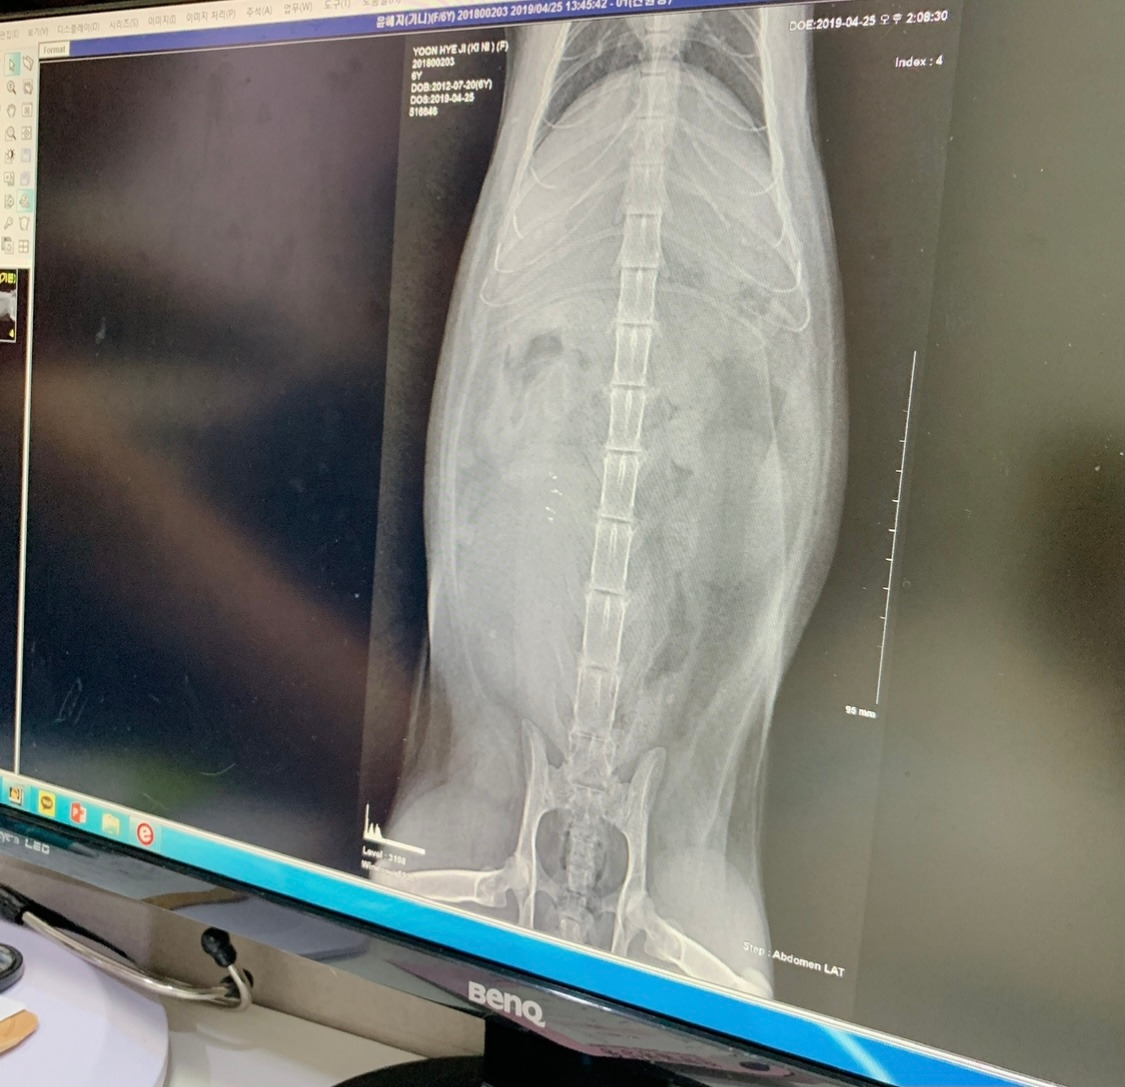

또 다른 질병인 치아흡수성병변은 고양이 충치인데 원인을 알지 못한다고 합니다. 지인 집사님네 고양이가 이 병에 걸려 아주 조금 공부를 해본 적이 있는데요. 치아가 부서지고 치아내 신경이 그대로 노출돼서 염증과 치통이 엄청 심한 병이라고 합니다. 이가 너무 아프면 침을 흘리고 밥을 도통 먹지 못해 야위어갑니다. 빨리 동물병원에 가서 X-ray 검사를 받고 치아를 뽑는 것으로 치료를 할 수밖에 없다고 합니다.